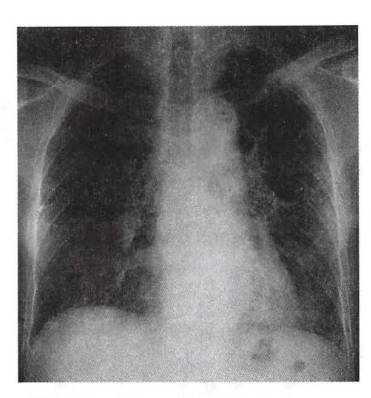

1. X线检查:期常规胸部X线平片不能显示异常,随着病情的进展,95%的患者出现症状时均有胸片的异常,X线表现为云雾状、隐约可见微小点状的弥漫性阴影,犹如磨玻璃(如下图);进一步进展则纤维化表现愈加明显,从纤细的网织状到粗大的网织状,或成网织结节状,以双下肺和外周(胸膜下)明显;晚期更有大小不等的囊状改变,即蜂窝肺,肺容积缩小,膈肌上抬,叶间裂移位。

特发性肺纤维化